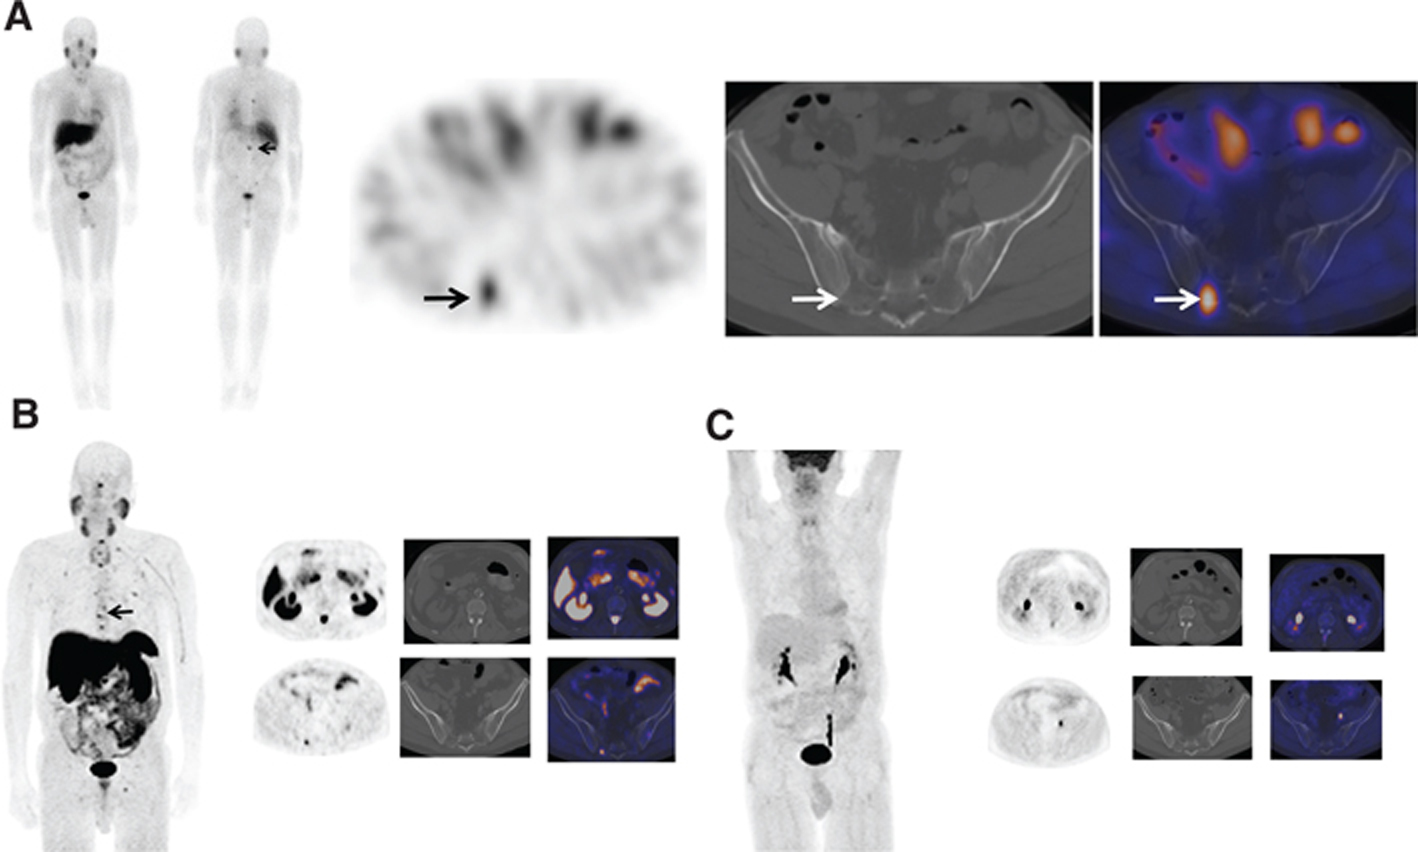

SPECT/CT improves sensitivity and specificity (Figure 6); in one case series, MIBG SPECT/CT was shown to increase diagnostic certainty in 89% of discordant CT and planar MIBG cases (41, 42).

Fig 6

Figure 6 A 40-year-old male patient with elevated catecholamines. (A) Whole body planar images, (B) coronal and axial attenuation-corrected SPECT images, and (C) axial non-enhanced CT and fused SPECT/CT images of the right adrenal region demonstrate a 4 cm × 3 cm × 4 cm soft tissue lesion with intense I-123 MIBG uptake much greater than hepatic uptake consistent with a biopsy-proven pheochromocytoma.